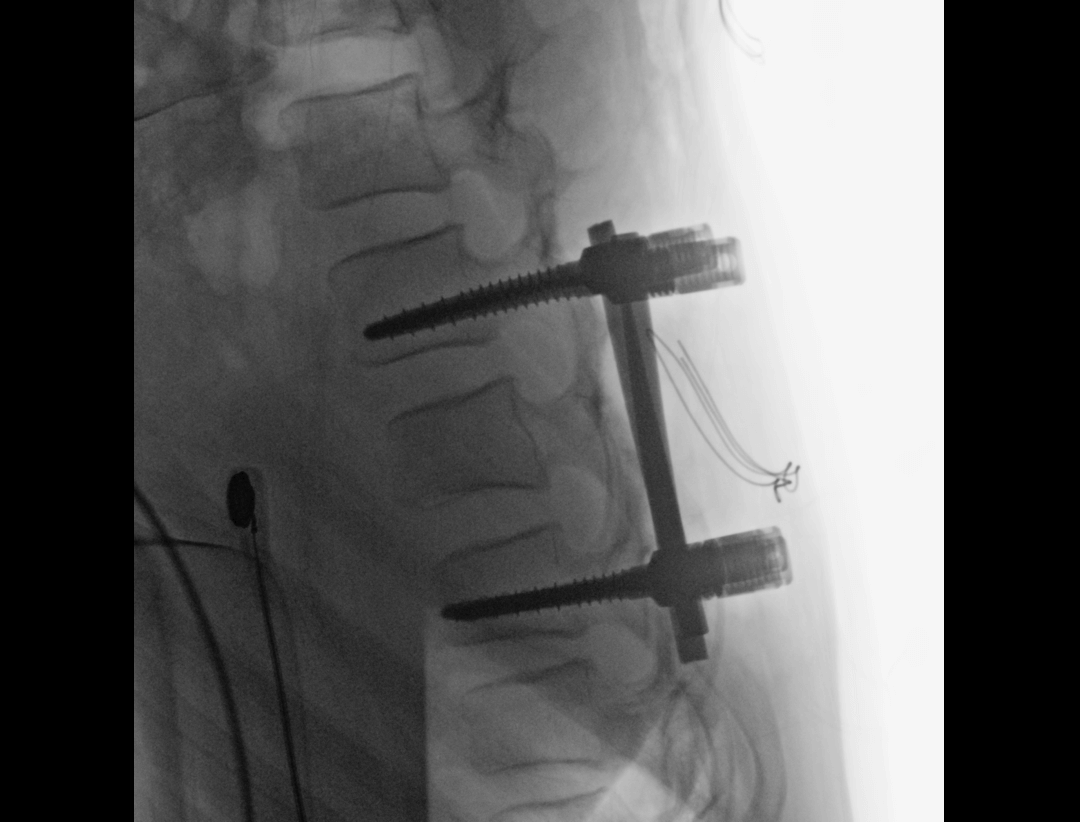

Przezskórna transforaminalna discektomia endoskopowa